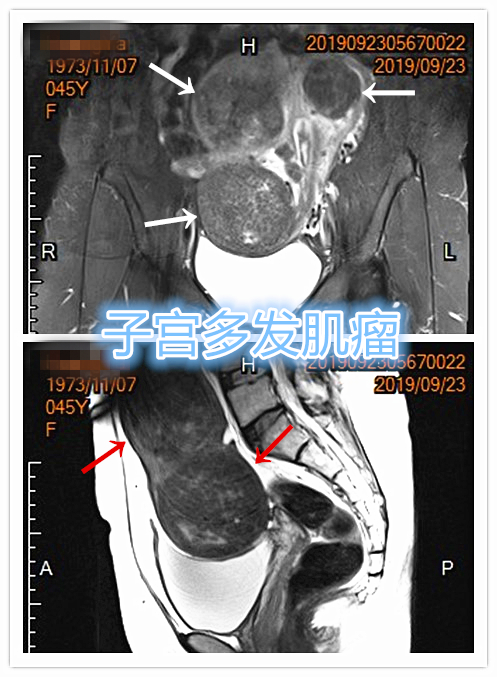

中年女性,发现子宫肌瘤进行性增大5年余。彩超提示多发、巨大子宫肌瘤,肌瘤外突明显,最大者直径近10cm。近半年尿频、尿急症状进行性加重,考虑增大的子宫肌瘤压迫膀胱所致。

- 盆腔磁共振检查显示显示多发巨大子宫肌瘤,部分突出浆膜外,明显压迫膀胱。

MRI显示多发子巨大宫肌瘤,压迫膀胱

冠状位

矢状位